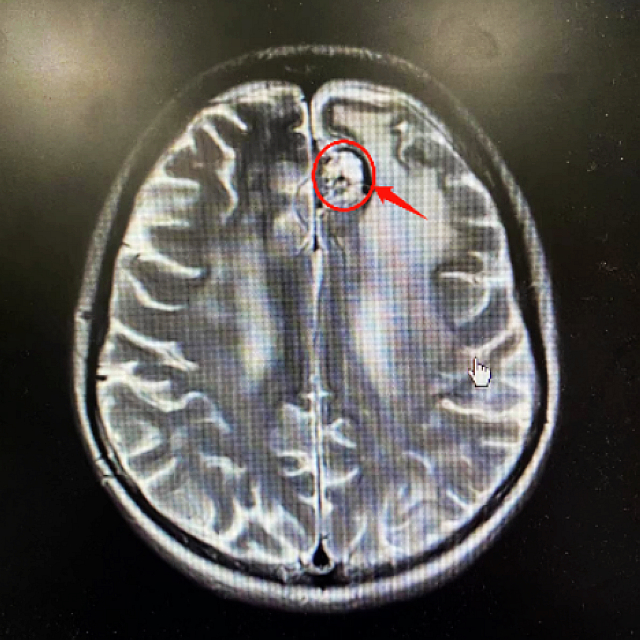

医生与唐阿姨及女儿沟通后,予以“特瑞普利240mg”免疫治疗联合“达卡巴嗪500mg”方案化疗,并针对颅脑病灶调强放疗(IMRT)。经过放化疗后,唐阿姨颅内的肿瘤稍有缩小,头晕、头痛、乏力、反应迟钝等症状也有所缓解。

经过5个周期的治疗,奇迹出现了:唐阿姨的颅内肿瘤、右侧大腿皮下肿瘤大小均较之前有明显缩小,也没有了头晕、头痛等症状,生活能自理,病情明显好转。